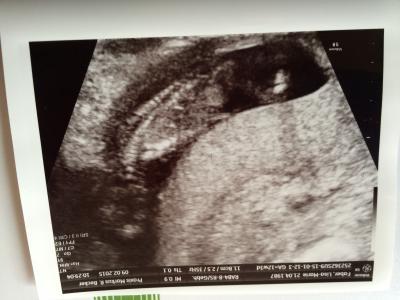

Alles ist in Ordnung Kind ist gut entwickelt 5,7 cm ca. Herz hat geschlagen Kindsbewegung ist auch da! Hat sich paar mal gedreht war schwer zu untersuchen da es sich ständig gedreht hat! Geschlecht hat er uns noch nicht genannt darf er auch nicht meinte er! Dann warten wir noch vier Wochen dann wissen wir es sicher! Hoff ich zumindest! Hab ihm mit geteilt das ich immer noch unterleibschmerzen habe! Vorallem beim arbeiten! Er meinte es könnte vom Kaiserschnitt noch kommen! Da ich ja auch die Gebärmutter eine Narbe hat und das kann schon zu Schmerzen führen! Ist aber 7 Jahre her der Kaiserschnitt!!!! Er wollte mich dann für 14 Tage mal krank schreiben! Ich möchte jetzt erst mal mit meinem Chef sprechen! Ob er mich in einem anderen Bereich der Filiale einsetzten kann! Ansonsten lass ich mich krank schreiben! Den das viele beugen und Strecken macht kein Spaß mit Schmerzen! Heute 12+3 Foto ist nicht so toll diesmal!

Bild zu Heute Frauenarzt Besuch der zweite - Forum für August - Mamis